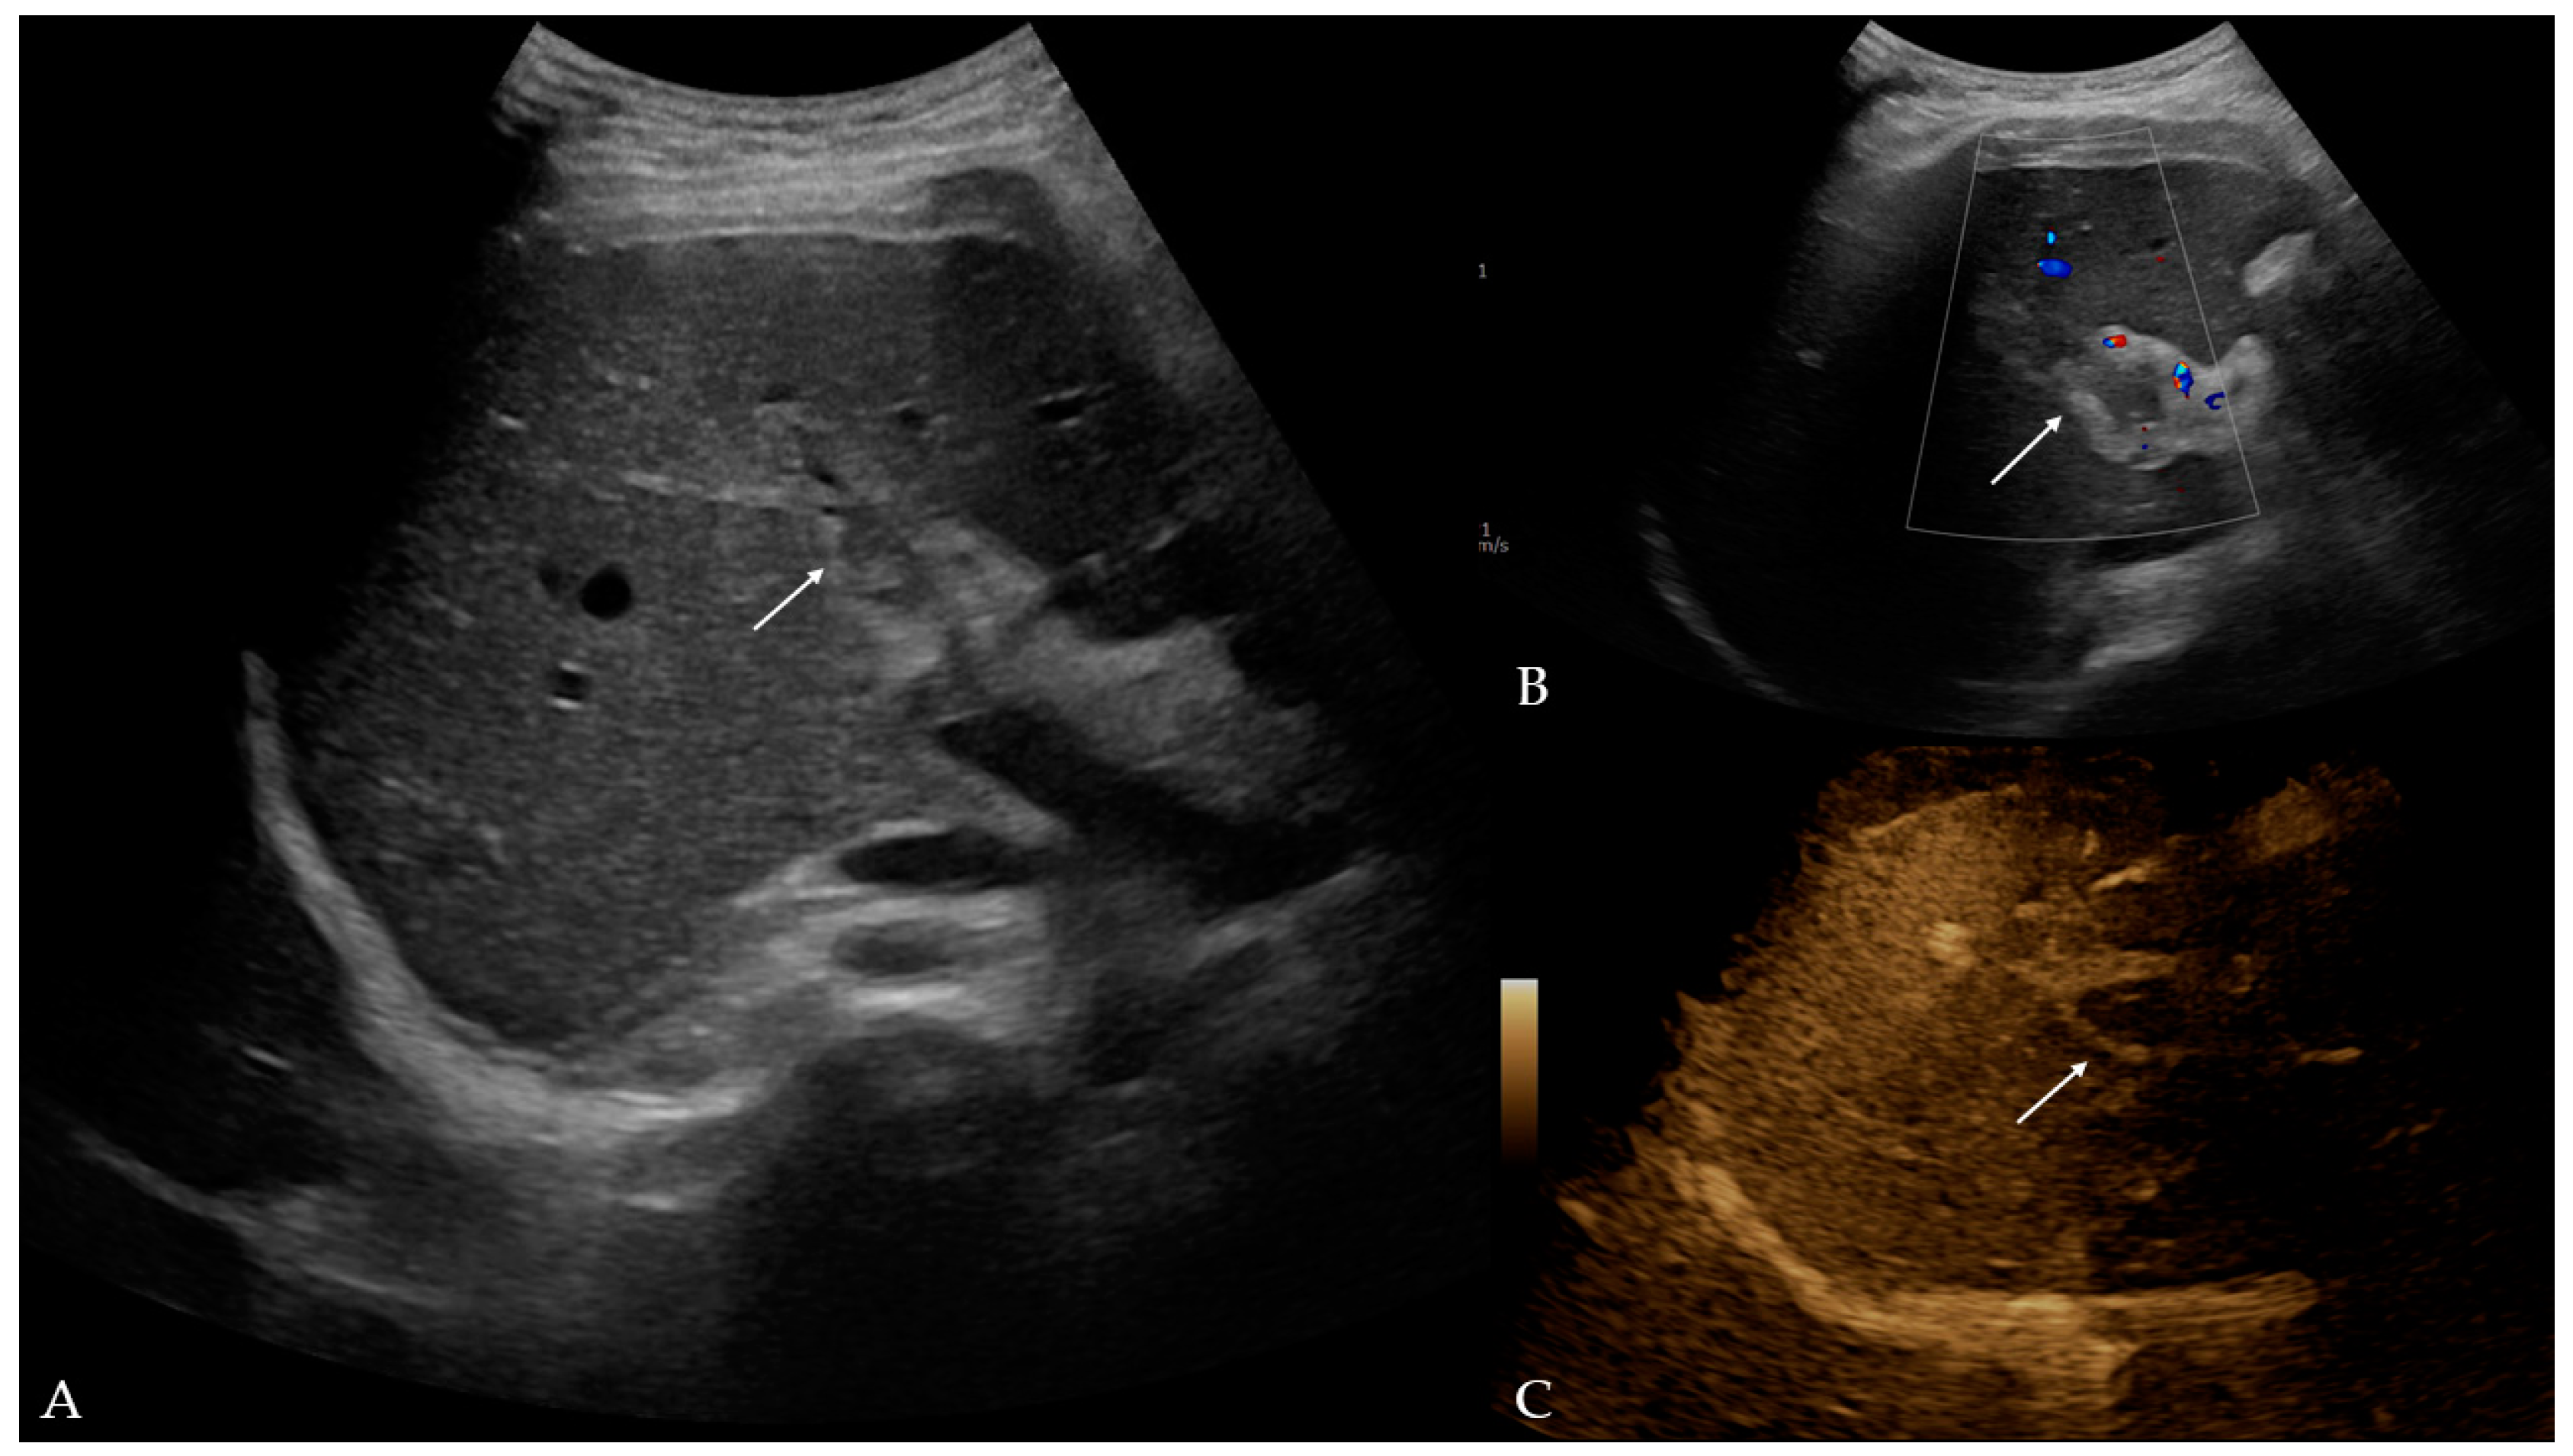

Twelve days later, the patient presented to the ED with a two-day fever (38 °C) and no other symptoms. The postoperative scar and ileostomy were unremarkable, and no signs of peritonitis were detected on clinical examination. Laboratory blood tests showed leukocytosis [15.56 (3.4–9.7 × 109/L)] with neutrophil predomination [10.99 (2.06–6.49 × 109/L)] and elevated liver enzyme [AST 63 (11–34 U/L), ALT 153 (8–41 U/L), GGT 220 (9–35 U/L), ALP 185 (54–119 U/L)] and CRP levels [99.6 (<5 mg/L)]. Other parameters were within the normal values. The attending surgeon referred the patient to the transabdominal US under suspicion of fluid collection. The US and color Doppler (CD) analysis showed left portal vein thrombosis and preserved patency of the hepatic arteries, veins, and inferior vena cava (Figure 1). No free fluid or collection was found. The patient was then referred to contrast-enhanced abdominal and pelvic CT to evaluate the extent of the thrombosis (Figure 2). The left branch of the portal vein was occluded entirely, and the segmental branch of the right portal vein was partially occluded. Thrombotic content was also found in the inferior mesenteric vein. No free fluid, collection, or liver and bowel perfusion abnormalities were found. Due to the described findings and recent diverticulitis, pylephlebitis was the imaging diagnosis. The patient was admitted to the hospital and put on low-molecular-weight heparin (LMWH) and intravenous administration of antibiotics (meropenem).

Figure 1.

Ultrasound and color Doppler of liver with addition of B-flow option: (A) B-mode—hyperechogenic material in lumen of left portal branch, potentially indicative of thrombus (arrow); (B) color Doppler—no Doppler signal in left portal branch, which corresponds to thrombus (arrow); (C) B-flow—no flow in left portal vein, which confirmed earlier findings (arrow).